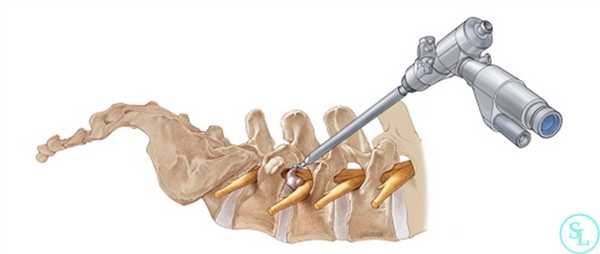

Этот вид хирургического вмешательства уже давно широко используется по всему миру и признан самым щадящим способом удаления патологически измененных тканей. Он подразумевает выполнение разрезов, размеры которых не превышают 1-1,5 см.

Через них в тело пациента вводится телескопический зонд и эндоскопическая трубка, являющаяся проводником для всего необходимого хирургические инструменты, посредством которых и резецируются измененные ткани в требуемом объеме. Современное оборудование дает возможность добиться высочайшего уровня увеличения операционного поля с высокой четкостью изображения, передающегося с введенной в тело видеокамеры на монитор в режиме реального времени.

- Через разрез в безопасную зону позвоночного пространства вводится расширитель под контролем ЭОП. По нему погружается рабочая гильза, сквозь которую проводят трубку эндоскопа. Ее диаметр составляет 6-8 мм. Подключают светодиод и камеру, моментально начинающую трансляцию изображения на монитор.

- Под многократным увеличением с помощью специальных инструментов, вводимых в операционное поле через трубку эндоскопа и сменяемых в ходе операции, нейрохирург выполняет резекцию патологически измененных тканей. Он последовательно устраняет образование, ставшее причиной развития компрессионно-вертебрального синдрома. Так для резекции костных остеофитов используются специальные кусачки, а для удаления грыжи межпозвоночного диска - микрощуп.

Эндоскопический вид

Эндоскопическая операция в нейрохирургии позвоночника применяется сравнительно недавно, за рубежом ее начали внедрять в средине 90-х, в России только спустя 10 лет. Эндоскопия по поводу декомпрессии - это самая миниинвазивная методика резекции патологических тканей через незначительный разрез (1-1,5 см) с использованием телескопического зонда и комплекта инструментов, которые вводятся в его рабочую полость. Сеанс длится в среднем 45 минут. На реабилитацию уходит примерно 60 суток.

Методика, когда хирург производит резекционные мероприятия через тонкую эндоскопическую трубку диаметром всего в 6-8 мм, является наиболее корректной по отношению к здоровым кожным и окружающим мышечно-связочным структурам. Благодаря этому пациент легче и быстрее переносит восстановительные этапы.

Эндоскопия предельно минимизирует риски интра- и послеоперационных осложнений за счет высочайших возможностей увеличения операционного поля с четкой передачей его изображения на хирургический монитор в реальном времени. Оперативное вмешательство с эндоскопом также располагает уникальными способами доступа:

Составить представление о том, как эндоскопическим методом производится освобождение сдавленных составляющих элементов нервной и кровеносной системы в позвоночнике, вам поможет информация:

- Как правило, операция проходит под местной анестезией, но возможно и использование общего эндотрахеального наркоза.

- Далее следует обработка антисептическим раствором кожных покровов спины, если доступ создается сзади. На коже в проекции места поражения выполняется маленький разрез (не более 1,5 см) скальпелем.

- В созданное отверстие под контролем ЭОП в безопасную зону позвоночного пространства вводится дилататор (расширитель), затем по нему вводится рабочая гильза, и уже через гильзу устанавливают трубку эндоскопа. В основном приборе подключают камеру и световод.

- Под многократно увеличенным видеонаблюдением, используя сменные инструменты, которые помещаются внутрь эндоскопа, хирург выполняет необходимые манипуляции. Специалист аккуратно удаляет источник компрессионного синдрома, например, остеофиты костными кусачками, грыжу диска микрощупом. Таким образом, достигается декомпрессия нервов или сосудов, которые смогут восстановиться уже в скором времени.

- Иссеченные структуры выводятся через отсек эндоскопической системы, полость позвоночного канала тщательно промывается физиологическим раствором от хирургического «мусора». Далее прибор извлекается, после чего ранку дезинфицируют и накладывают на нее несколько швов.